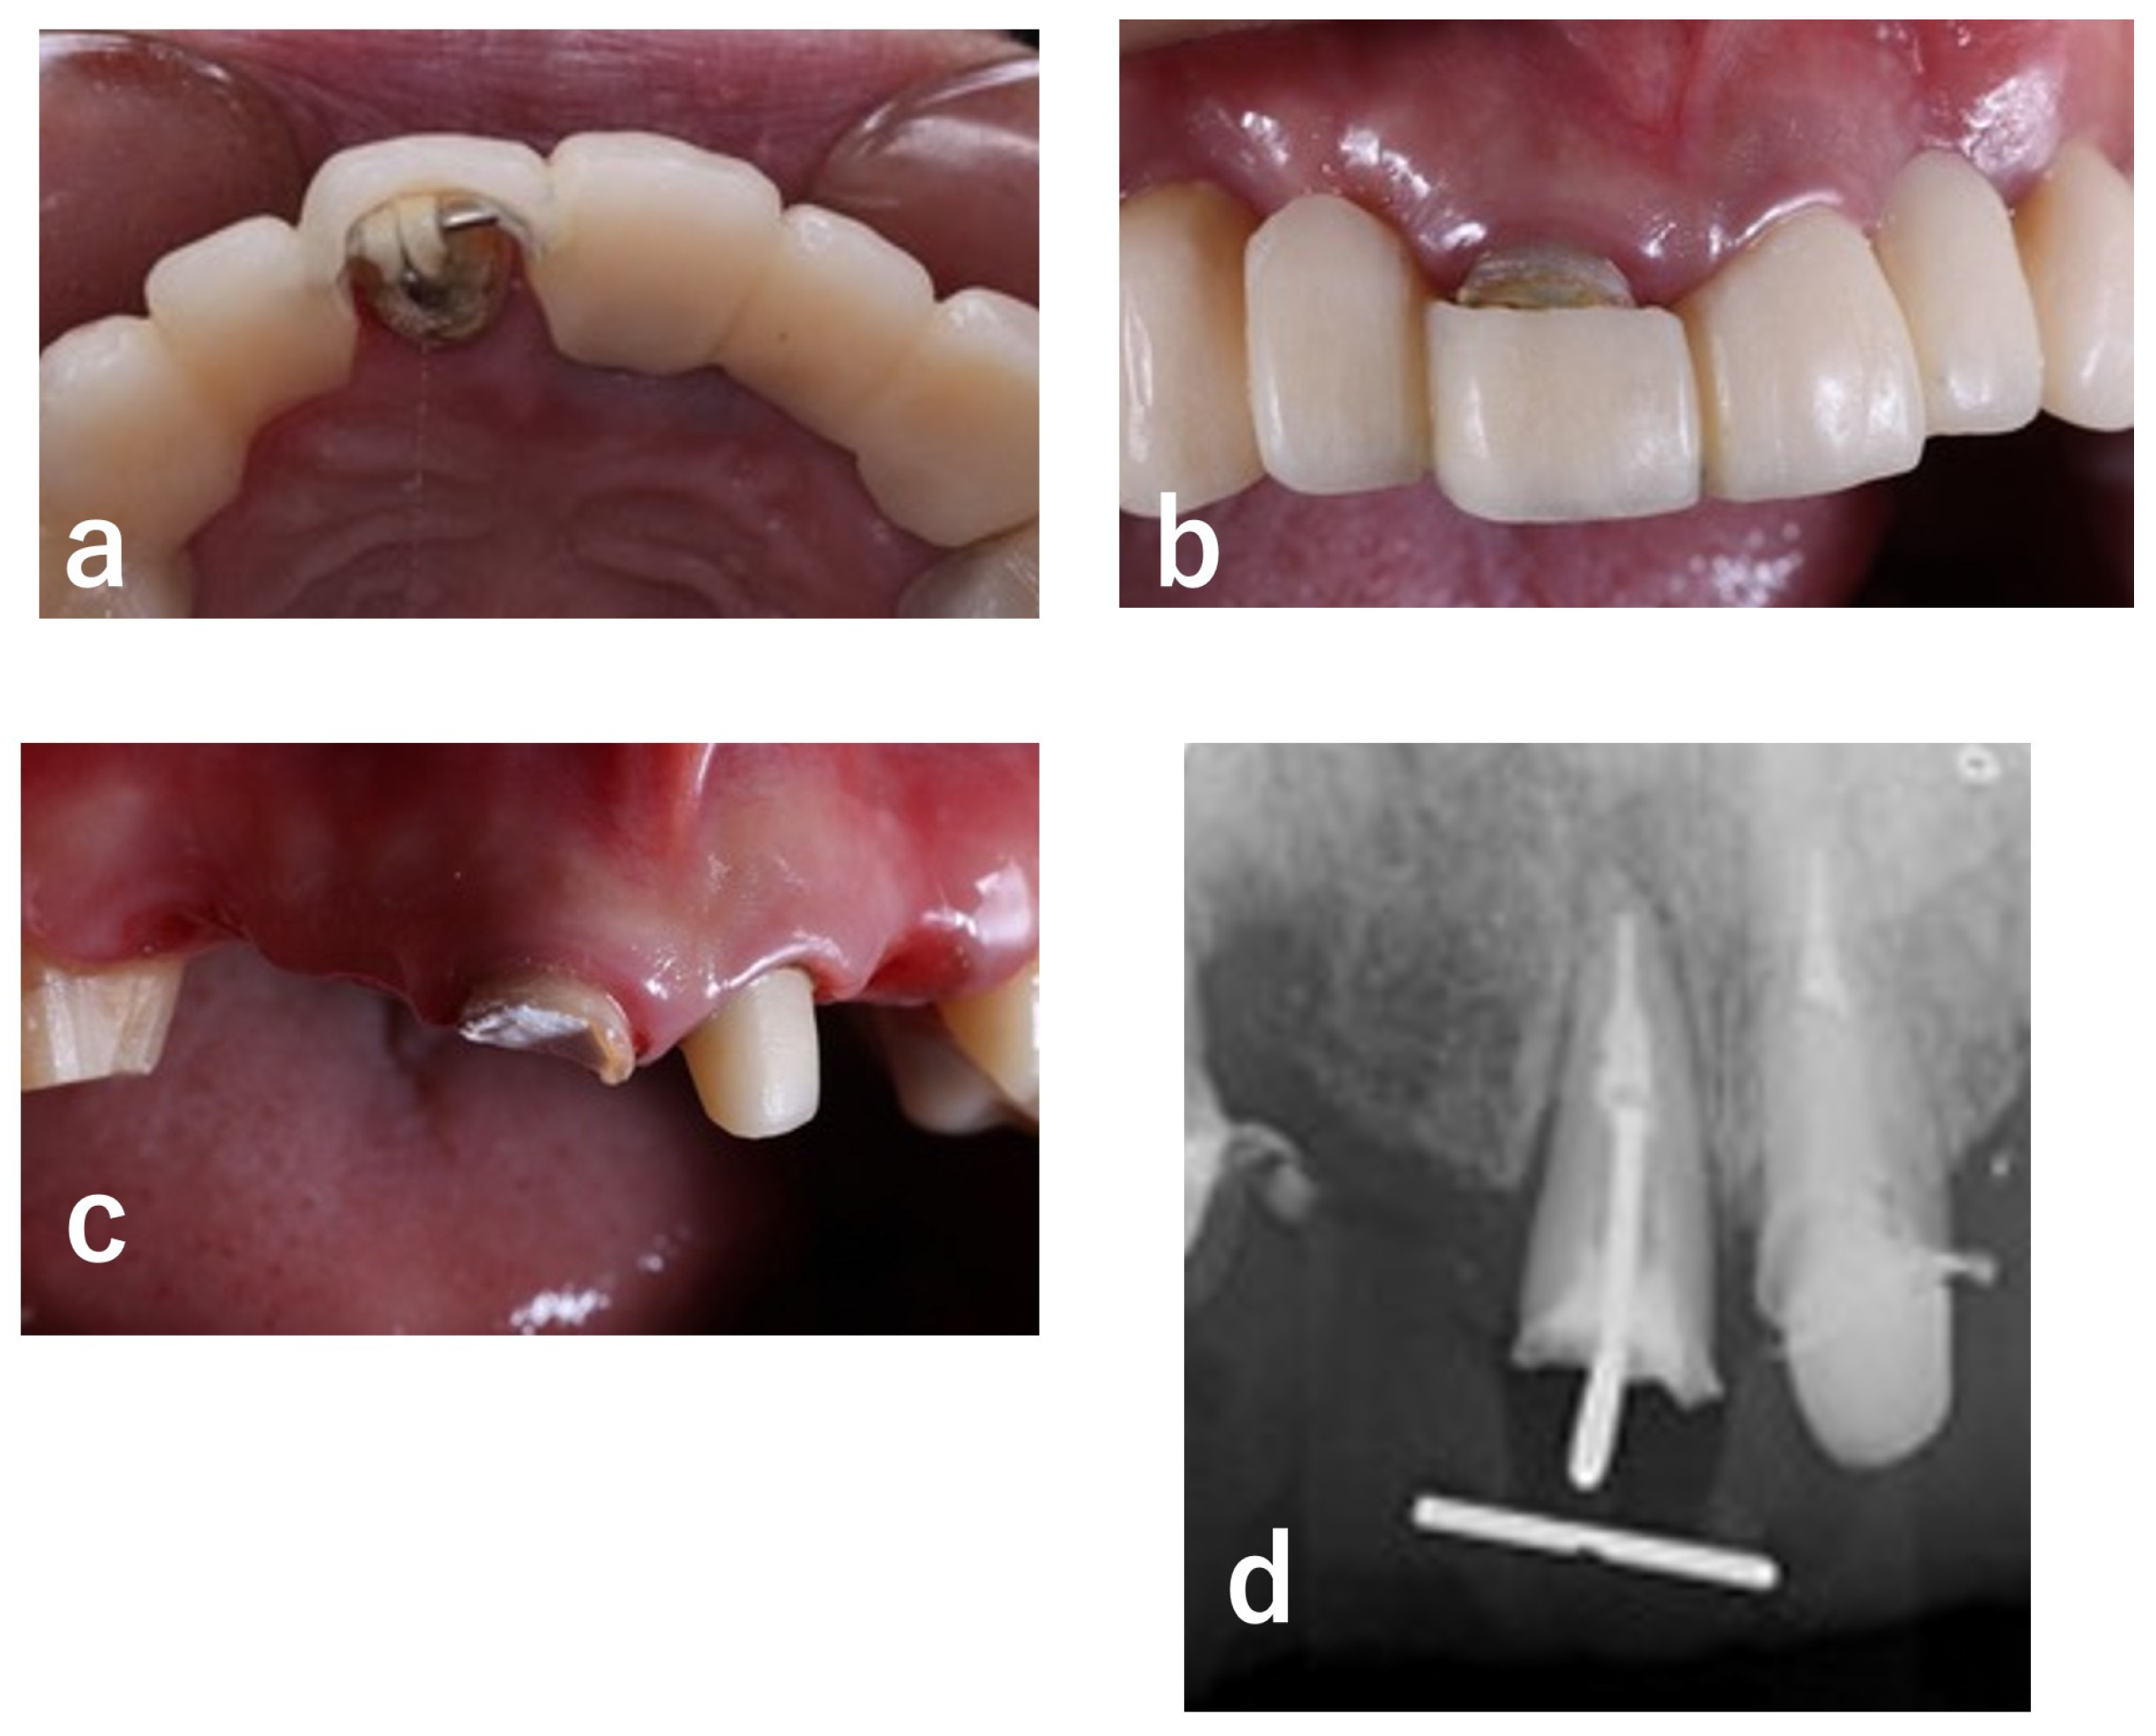

| 1 | Initial visit (August 2015) | Initial assessment & provisionalization | Assessment after traumatic event; long-span provisional restoration to re-establish posterior support and stabilize occlusion (Figure 1 and Figure 2) |

| 2 | Shortly after initial visit | Extraction of #13 | Vertical root fracture confirmed; extraction indicated (Figure 3) |